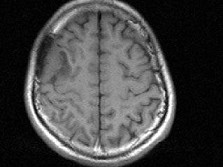

男,48岁,发作性口角抽搐半月,根据所提供图像,最可能的诊断是()

男,48岁,发作性口角抽搐半月,根据所提供图像,最可能的诊断是()

[单选题]男,48岁,发作性口角抽搐半月,根据所提供图像,最可能的诊断是()A . 右额叶胶质瘤B . 右额叶非典型脑膜瘤C . 右额叶骨瘤D . 右额叶炎性肉芽肿E . 右额叶转移瘤

- 查看答案